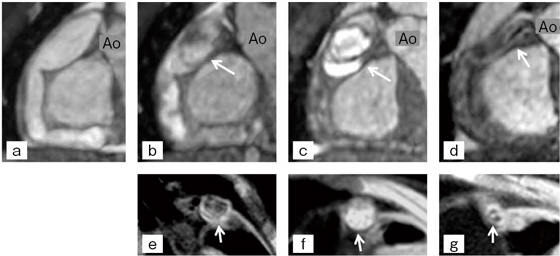

3歳8か月時川崎病発症男児で,2004年10月より,約半年ごとにMRCAによる経過観察を施行している。初回MRCAで,右冠動脈瘤が起始部から末梢まで続くことが明瞭に確認された(図5 a)。しかし,半年後の経過観察にて,balancedシーケンスにて瘤内信号の不均一性(図5 b),またBBシーケンスにて瘤内血栓の出現が示された(図5 e)。さらに,半年後の2004年9月のbalancedシーケンスで,異常な高信号を瘤内に認め(図5 c),BBシーケンスにおいても高信号を伴い,血栓性閉塞瘤が確認された5)(図5 f)。発症から1年半後の,2006年4月の5歳時でのMRCA撮像では,前回の検査時に認めた血栓信号は描出されず,右冠動脈瘤内に数本の再疎通血管が確認された(図5 d,g)。約2年間で,本症例は冠動脈瘤⇒瘤内血栓⇒閉塞瘤⇒再疎通血管と血管形状が変化する状態を,MRCAにて経時的に描出し得た。

図5 症例2:3歳8か月時川崎病発症男児

c,d:MRI冠動脈画像